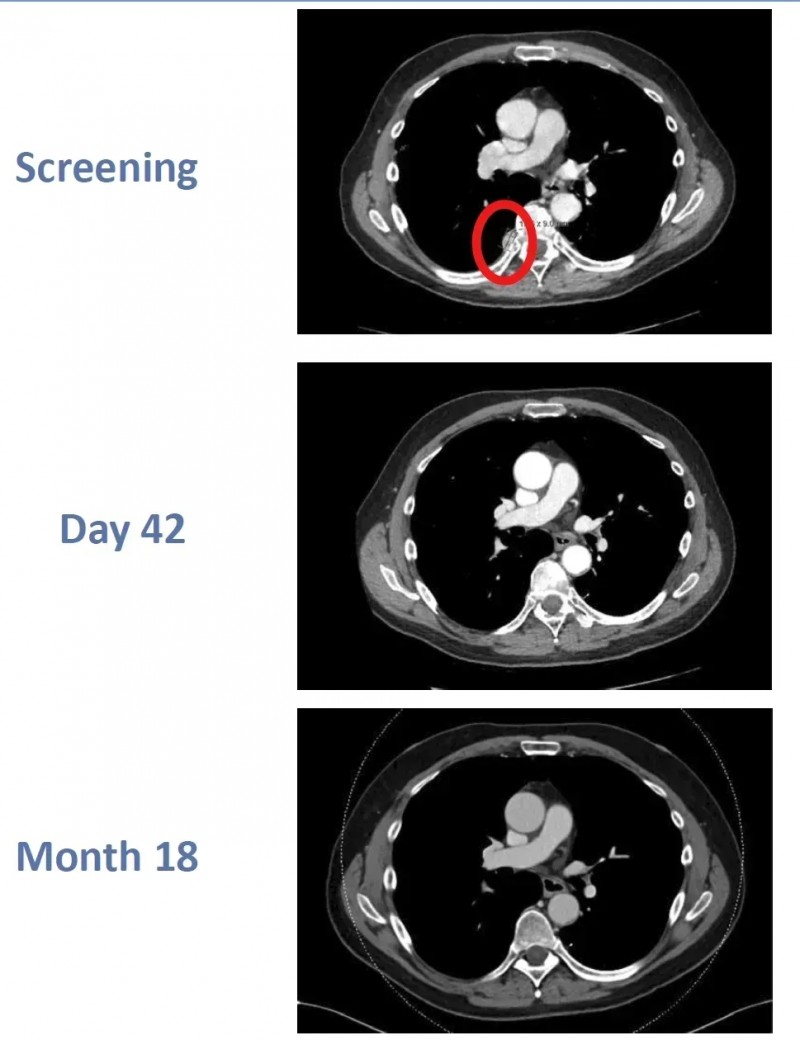

该患者是一位64岁男性,确诊ccRCC后接受阿替珠单抗联合卡博替尼治疗,病情仍复发并转移至肺部、胸膜,随后入组该临床试验。接受CTX130治疗后,患者先达到部分缓解(PR),治疗第3个月便实现完全缓解(CR),且这一状态持续稳定,至治疗第18个月复查时,完全缓解状态仍未改变。

▲图源“BMJ”,版权归原作者所有,如无意中侵犯了知识产权,请联系我们删除

此次临床试验首次报道了肾细胞癌患者通过CAR-T疗法获得完全缓解的案例,不仅印证了CTX130的显著疗效,更进一步证实了CAR-T细胞疗法在实体瘤治疗领域的巨大潜力。